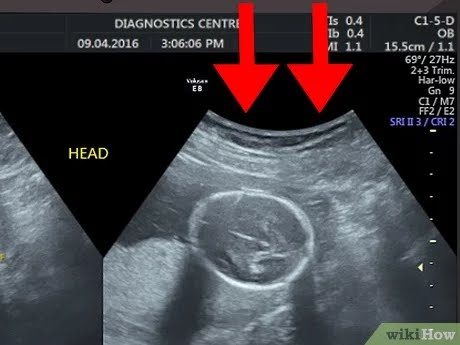

अपनी गर्भावस्था की अल्ट्रासॉउन्ड रिपोर्ट पढ़ने के लिए सबसे पहले हर अल्ट्रासाउंड में EDD (estimated delivery Date ) तथा LMP (लास्ट मेन्स्त्रुअल पीरियड )के बारे में जो भी जानकारी दी जाती है उसका मतलब यह है कि प्रेग्नेंट होने से पहले महिला की लास्ट पीरियड किस डेट में आयी थी और EDD का मतलब होता है डिलीवरी किस तारिख को हो सकती है, दरअसल मे डिलीवरी की तारीख पक्की नहीं होती है। लेकिन फिर भी अंदाजा लगाया जा सकता है कि डिलीवरी इस तारिख के पहले या आगे हो सकती है और लेबर पैन शुरू हो सकता है।